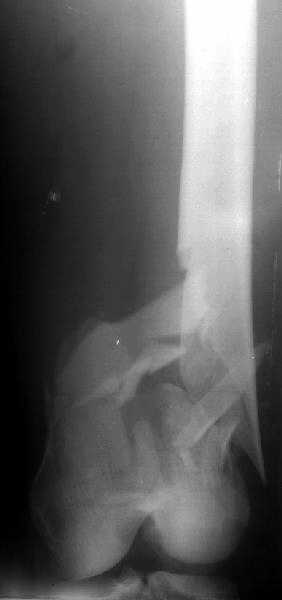

Отправитель: Alexander Chelnokov 28 Декабрь 2003, 21:01

1

2

de> you think you are using antigrade nails for some very low

de> fractures including some intercondylar fractures.

Exactly. It seems the option looks underestimated.

de> Do ou have a reference supporting antigrade nailing in such

de> occasio in favour of other choices eg DCS, Supracondylar nail,

No, i haven't seen such comparisons. However some advantages of closed antegrade nailing vs conventional plating looks self-evident like no site opeining, no bone skeletization, less blood loss, no need for autografting... If you or other colleagues can help me with the references it would be greatly appreciated. I would be interested also to compare ante- vs retrograde nailing for the localization.

de> And perhaps you could show us also some of your results ,

de> that is (follow up) not immediate postop x rays.

I attached an example of C2 fracture with result of the same technique in 5 months.

[ Ответить ]